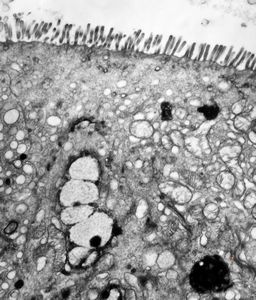

normal jejunal enterocyte

enterocyte - normal and celiacal microvilli

normal mucosa - jejunum - microvilli